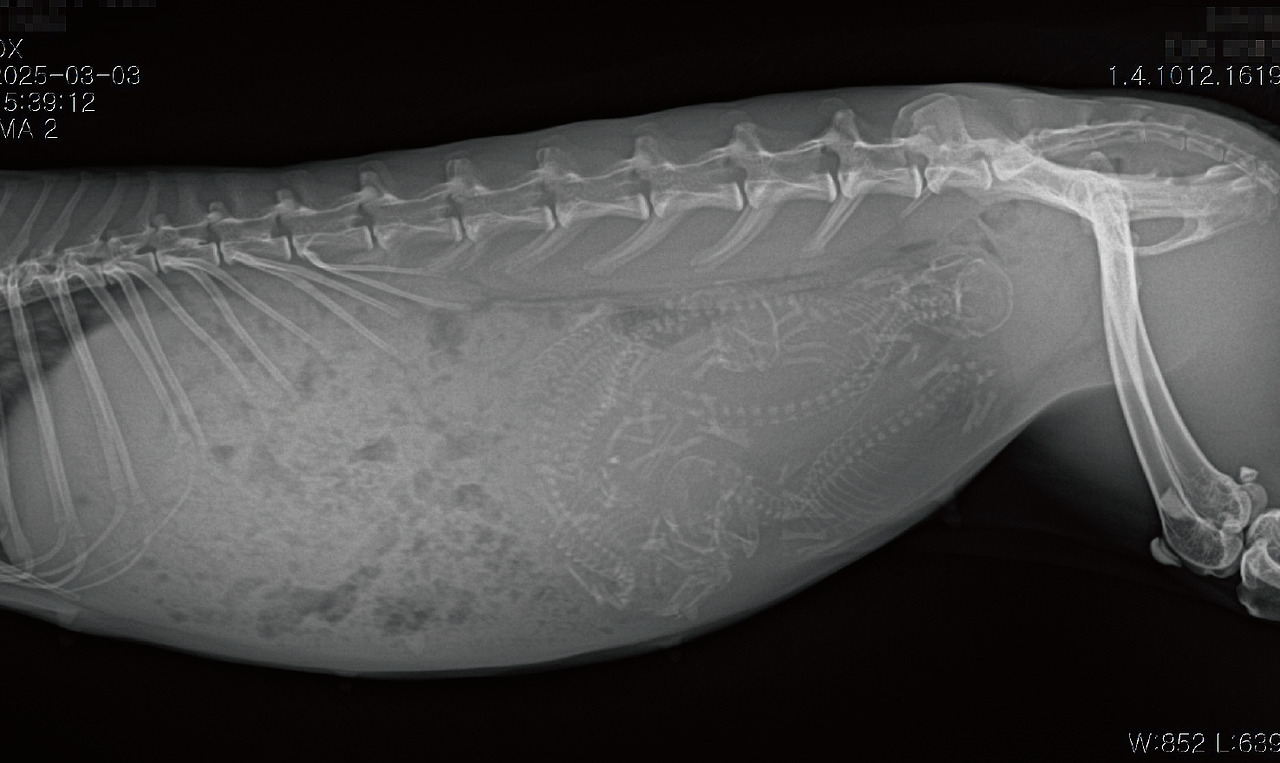

아이들을 품은 채 죽음을 맞이한 어머 토끼의 생전 X-ray 사진이나

질병으로 한쪽 눈을 덜어낸 토끼,

달리는 차에 목이 잘린 아이의 사진까지 관련 정보가 녹아있다.

실제 편집을 맡은 입장에서

오히려 어디까지 대중들에게 공개해야 충격이 적을 것인가를 고민했어야할 정도였다.